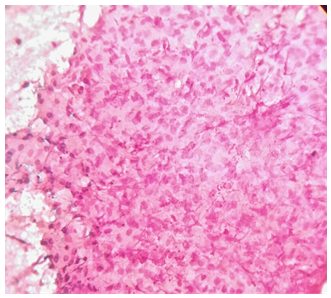

Utility of Ultrasonographically Guided Fine Needle Aspiration Cytology in the Diagnosis of Hepatic Masses

Dr. Prema Saldanha,, Dr. Thahseena Abdulla